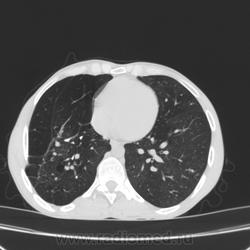

Состояние после торакопластики.

Молодой человек 30 лет, в 04 году выявлен фиброзно-кавернозный ТБ, в течение 12 месяцев лечился в стационаре, прооперирован-5реберная торакопластика справа, через 3 года переведен в 3ГДУ, в 10году снят с ДУ по излечению. Пришел провериться по ухудшению состояния. На КТ легких данных за рецидив ТБ, вроде нет. С " торакопластикой" был единственным пациентом на учете.

Состояние после правосторонней 5-реберной торакопластики по поводу ФКТ.Грубые остаточные изменения:поликистоз,буллезно-дистрофические изменения,плевропневмоцирроз правого легкого..Нет ли  мелкоочаговой диссеминации в обоих легких?Нужен Rархив.(ПТД).

Нет, это кальцинаты и более плотные уже. Архив только пленочный, 8 лет назад "цифры" не было. Можно и пленку перефотать...